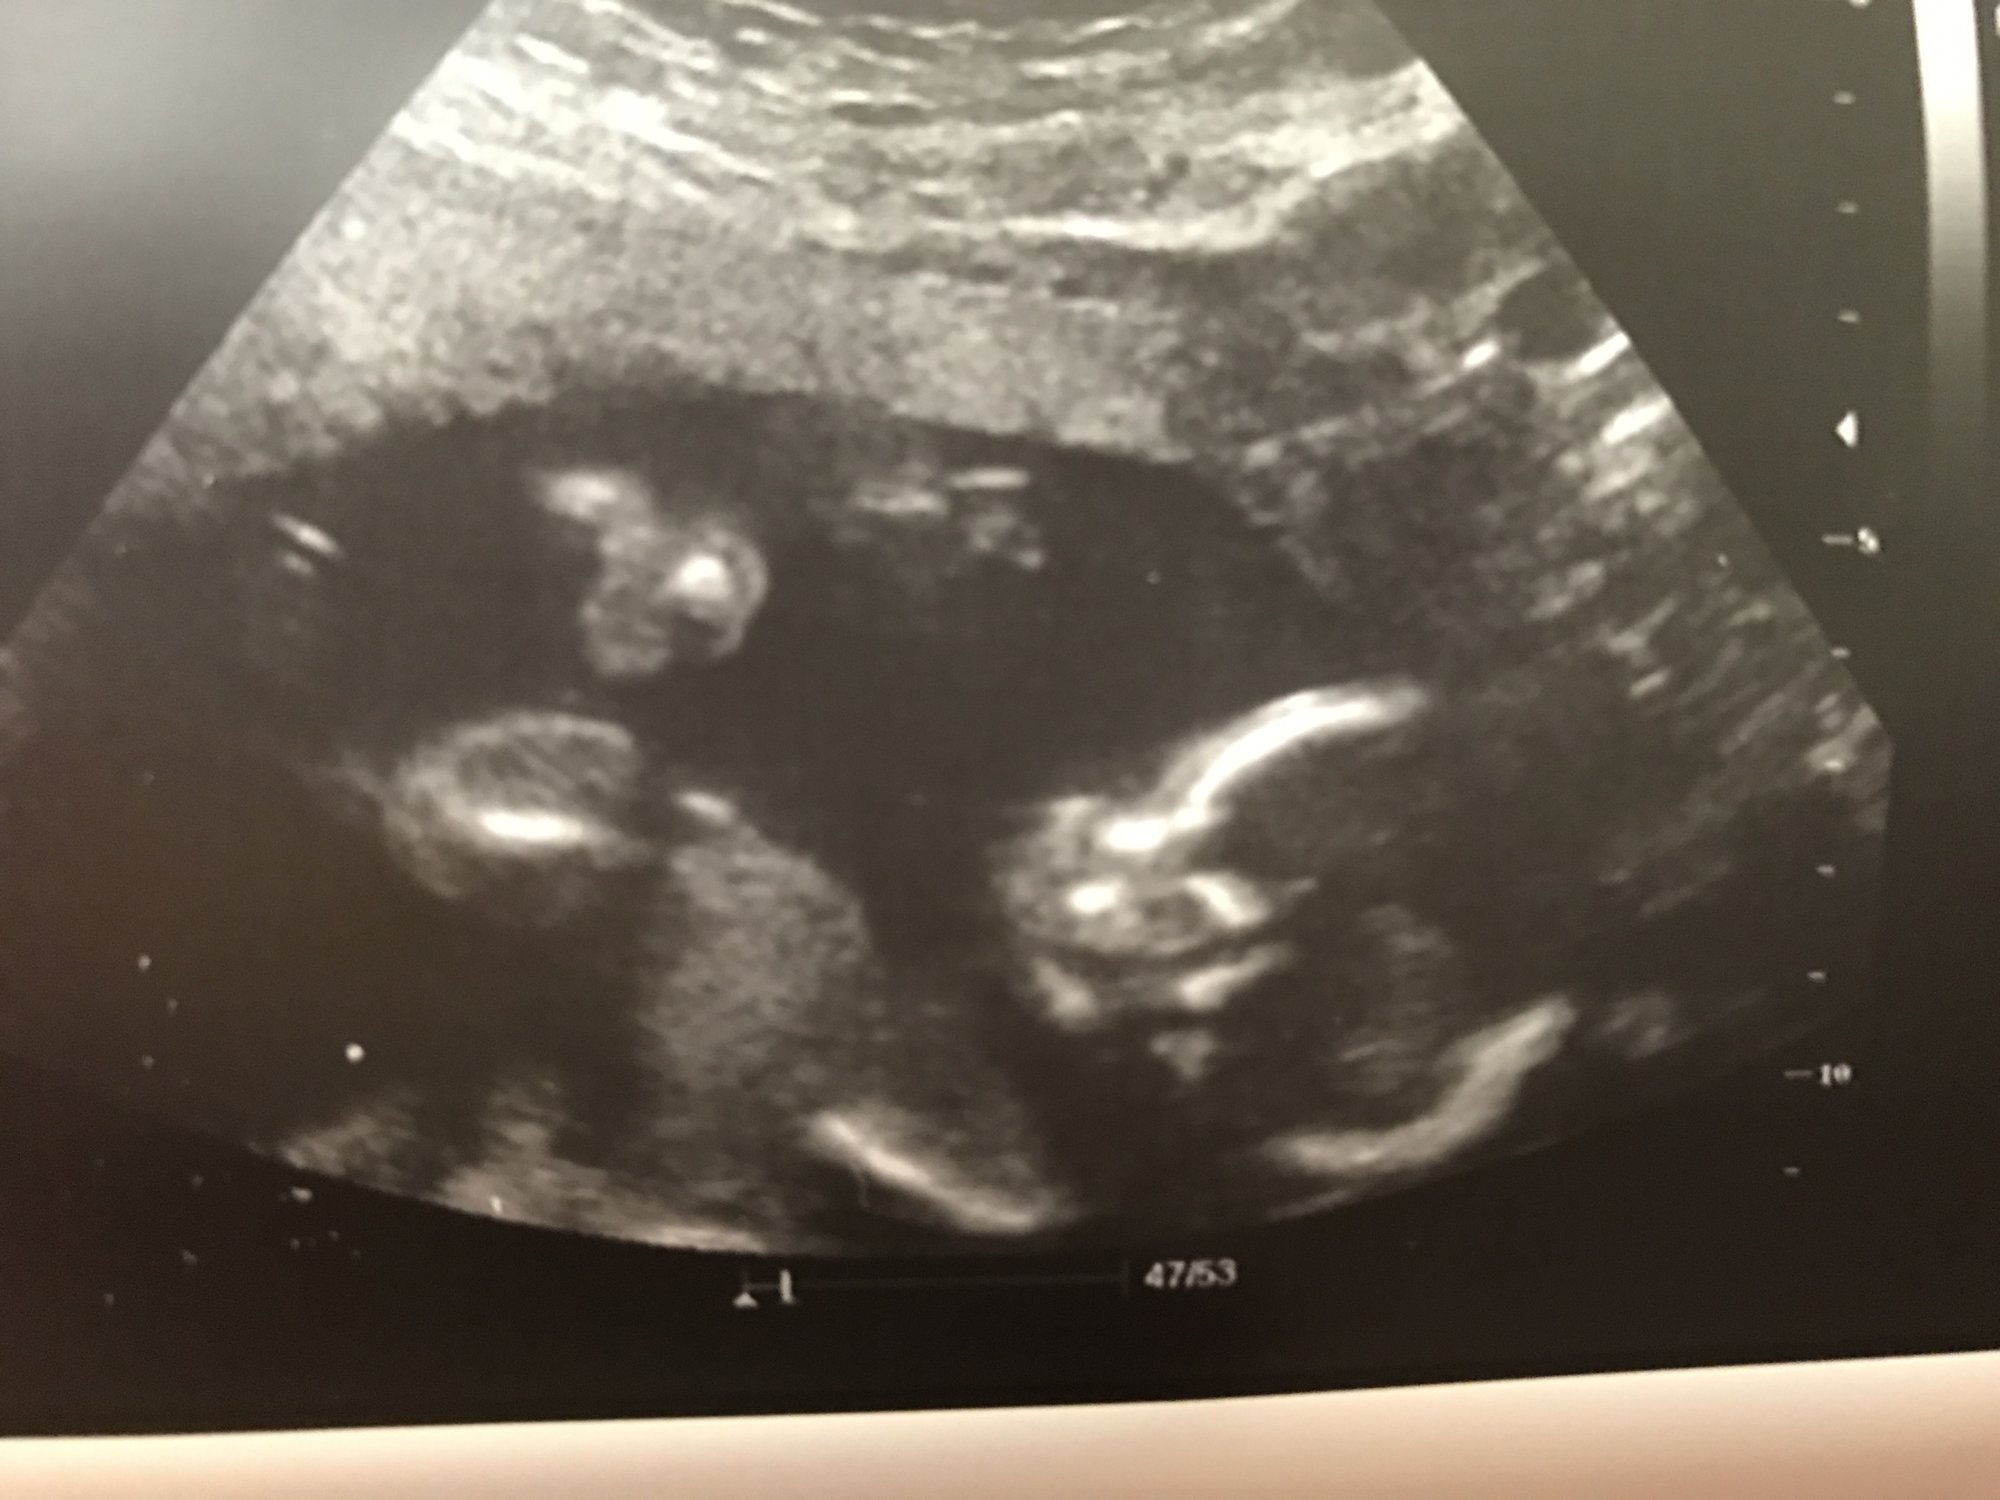

Little girl was so wiggly it was pretty blurry. Plus she basically looks like a creepy skeleton. Haha. But here she is, being pretty unladylike on the bottom right but proving she's a girl at least.